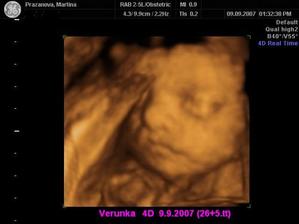

Dne 3.4.2007 to vypadá dle testů, že to vyšlo a my se snad dočkáme našeho vytouženého miminka a já nikdy nezapomenu děkovat a vážit si práce všeho personálu CAR u Apolináře. Dne 19.4.2007 nám bylo v CAR ultrazvukem potvrzeno, že opravdu čekáme naše vytoužené miminko. Dne 4.6.2007 jsme byli na genetickém UTZ ve 12+4.tt a UTZ dopadl na 1*. Dnes 26.7.2007 jsme byli na 3. ultrazvuku, jsme ve 20+2.tt a miminko je v naprostém pořádku. S maminkou už je to horši, ale snad všechno nakonec dobře dopadne. Dne 30.8.2007 jsme byli neplánovaně na 4. ultrazvuku a monitoru, protože maminka upadla na schodech, naštěstí je miminko v pořádku a neutrpělo žádnou újmu. Dnes 9.9.2007 jsme byli s tatínkem na 4D ultrazvuku v Gennetu Praha, máme krásné fotečky a DVD. Dozvěděli jsme se, že miminko v mém bříšku je holčička. Večer 9.9.2007 jsme naší holčičce vybrali jméno, je to Verunka.